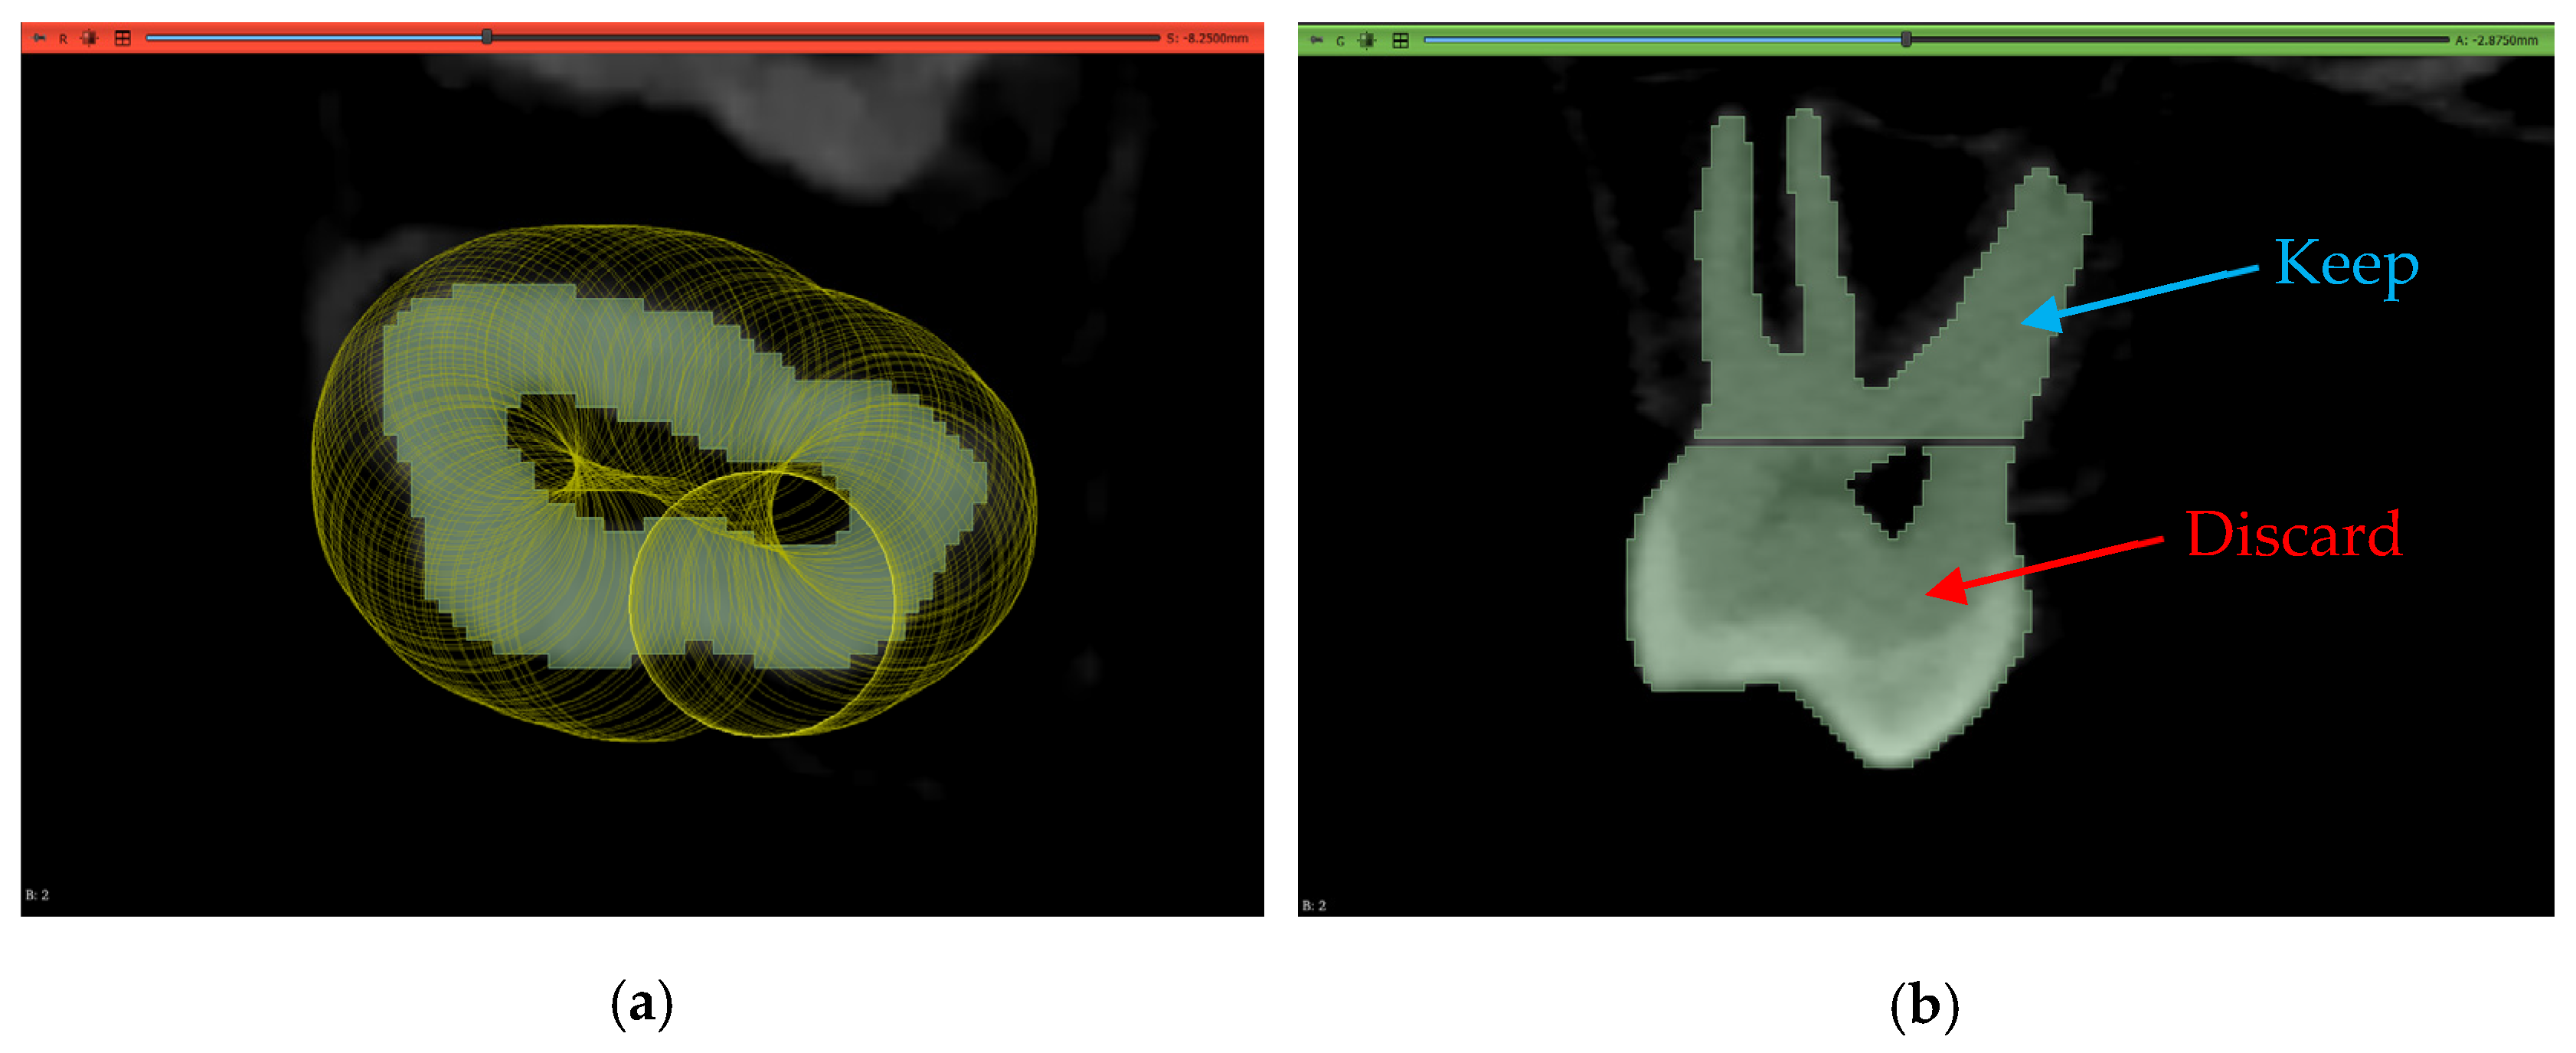

An acknowledged limitation of the extension by the authors is its inability to offer individual tooth labeling. Thus, a manual step was performed to isolate the tooth of interest by removing the connecting pixels to the adjacent teeth and then keeping the island of pixels belonging to the tooth while discarding all other islands. This is shown in Figure 16.

Figure 16.

The results of segmentation using the automated model: (a) initial connection between adjacent teeth immediately after running the model, (b) erasing pixels of connection, and (c) isolated tooth of interest.

After obtaining the 3D models, they were separated at the same height level using a similar isolation and island removal technique as that used in Section 2.5 to cleanly cut the models from the same plane. This is shown in Figure 20 for the maxillary second molar of Dataset 2. This process yielded another 150 models for the second line of comparison regarding the subgingival part of the teeth.

Figure 20.

The method of splitting the model to obtain the subgingival part: (a) erasing on layer in the transverse plane and (b) the ouput of erasure to split the model in the sagittal plane.